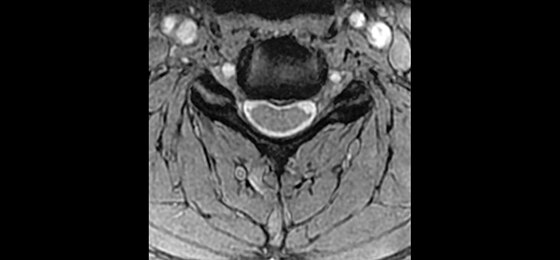

GEM Posterior Array - Embedded high-density posterior array with optimal coil element geometry that enhances spine, abdomen, cardiac, and lower extremity scanning.

GEM Anterior Array - A lightweight, flexible, thin and pre-formed array to embrace patients’ various sizes and shapes. With 54 cm of S/I coverage, the anterior array permits upper abdominal and pelvic imaging without repositioning the patient and supports parallel imaging in all 3 planes.